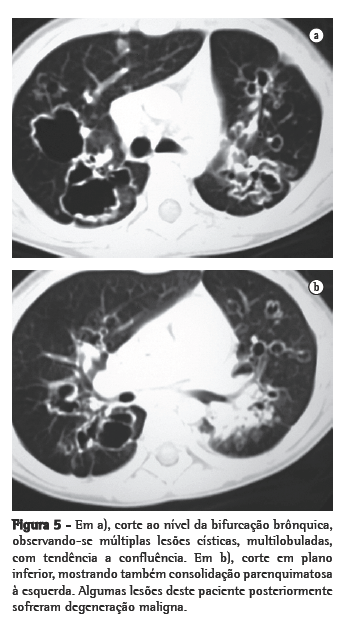

ResultadosNos 8 casos foram observadas na TC formações polipóides na traquéia. Em 1 deles, identificou-se também uma lesão em brônquio principal. Sete pacientes mostravam comprometimento do parênquima pulmonar. Em todos foram observadas lesões nodulares escavadas, com contornos internos irregulares, e paredes de espessuras variadas, com aspecto multilobulado em 6 casos, e com confluência das lesões em 5 deles (Figuras 1 a 5). Nódulos sólidos foram vistos em 6 pacientes, Em apenas 1 dos casos foram vistos níveis líquidos. As lesões predominaram nas bases em 3 pacientes, nos terços médios em 2, e em 2 não havia predomínio de distribuição. Em 1 dos pacientes, foi observada associação com massa, e em outro, com consolidação. Neste último paciente (Figura 5) foi constatada degeneração maligna em múltiplas lesões. Sinais de aprisionamento aéreo também foram observados em 1 caso. Em nenhum deles detectou-se linfonodomegalia ou derrame pleural.

A degeneração maligna para carcinoma de células escamosas é relatada entre 1% e 10% dos casos de PLTB,(3,4) em geral ocorrendo após a irradiação ou quimioterapia com bleomicina, ou em pacientes com história de tabagismo.(1,6) Pode acontecer na infância ou mesmo décadas após o diagnóstico de papilomas benignos.(4) Na maior parte dos casos, ocorre em pacientes com disseminação prévia da doença para a árvore traqueobrônquica. Raramente pode ocorrer na forma laríngea da doença.(2,5) Em 1 dos casos estudados, houve degeneração maligna, constatada em biópsias realizadas em três diferentes lesões.